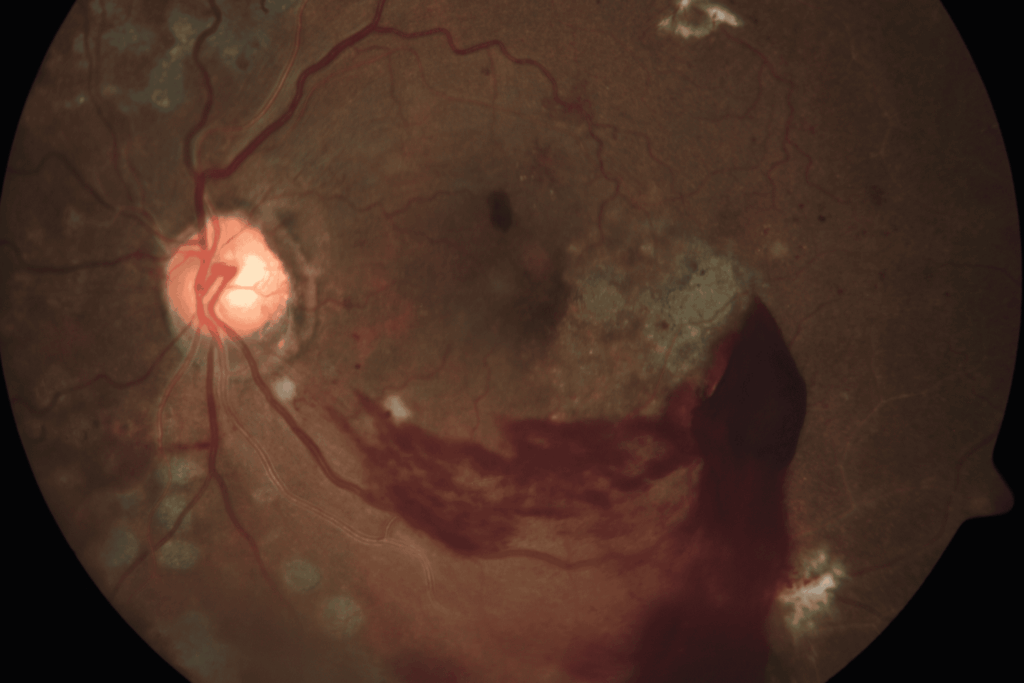

Proliferative Diabetic Retinopathy (PDR)

In some patients, diabetic retinopathy may progress from non-proliferative to proliferative. Proliferative diabetic retinopathy is characterized by neovascularization (neo = “new” and vascularization = “blood vessels”). That is, the appearance of new, fragile blood vessels on the optic nerve or retina’s surface. These new blood vessels frequently bleed into the vitreous cavity, causing hemorrhage. Furthermore, they may cause scarring on the retina, which can pull the retina, causing tractional retinal detachment. These new blood vessels are like “weeds in the garden” and may even grow in the front of the eye on the iris, causing a severe type of glaucoma to develop.

Unfortunately, the new blood vessels do not replace lost blood flow. Rather, they grow on the surface of the retina and cause vision loss in one of two ways:

Vitreous hemorrhage: A vitreous hemorrhage is bleeding into the eye. Instead of being filled with clear fluid through which one can see, the back of the eye is filled with blood, causing vision loss.

Tractional retinal detachment: The new blood vessels pull on the retina (create “traction”) and pull the retina off the eye wall (“retinal detachment”). The photoreceptors in detached retina cannot see and undergo damage, resulting in severe vision loss, sometimes irreversible vision loss